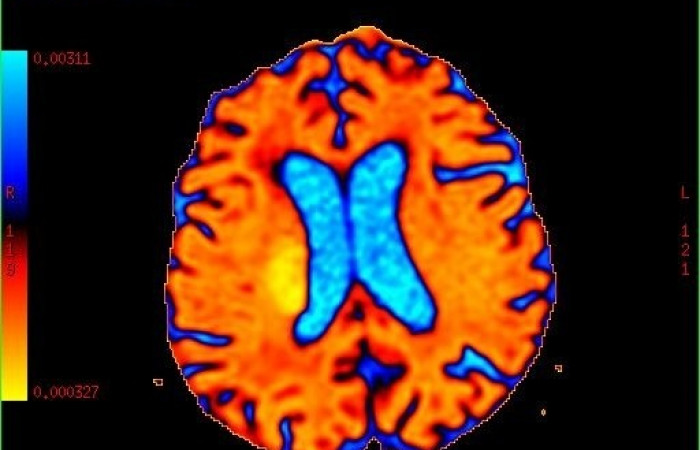

ˇ badanie perfuzyjne mózgu (z i bez środka kontrastowego)

ˇ badanie dyfuzyjne mózgu z traktografią

ˇ spektroskopia protonowa mózgu (HMRS)

ˇ spektroskopia fosforowa mózgu (PMRS)

ˇ czynnościowe obrazowanie mózgu (fMRI)

- Spektroskopia MR, która pozwala na przedstawienie patologii na poziomie metabolizmu, kiedy brak jest jeszcze zmian w obrazach morfologicznych. System umożliwia wykonywanie badań w opcji spektroskopii protonowej (HMRS) a także fosforowej (PMRS).

- Funkcjonalne obrazowanie MR (fMRI) mózgu, które umożliwia identyfikację ośrodków neuronalnych, odpowiedzialnych za czynności takie jak poruszanie kończynami, mowa, widzenie czy funkcje wyższe. Pozwala także na tzw. mapowanie przed zabiegami neurochirurgicznymi - ocenia się wzajemny stosunek guza do ośrodków neuronalnych odpowiadających za określone czynności w celu minimalizacji następstw zabiegu.

- Dyfuzja MR z traktografią pozwalającą na prezentację dróg nerwowych